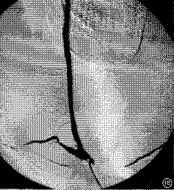

7.動脈造影,超聲都卜勒,ECT等檢查證明,受累的頭臂動脈和下肢動脈顯示狹窄或閉塞,降主動脈、腹主動脈呈縮窄表現。